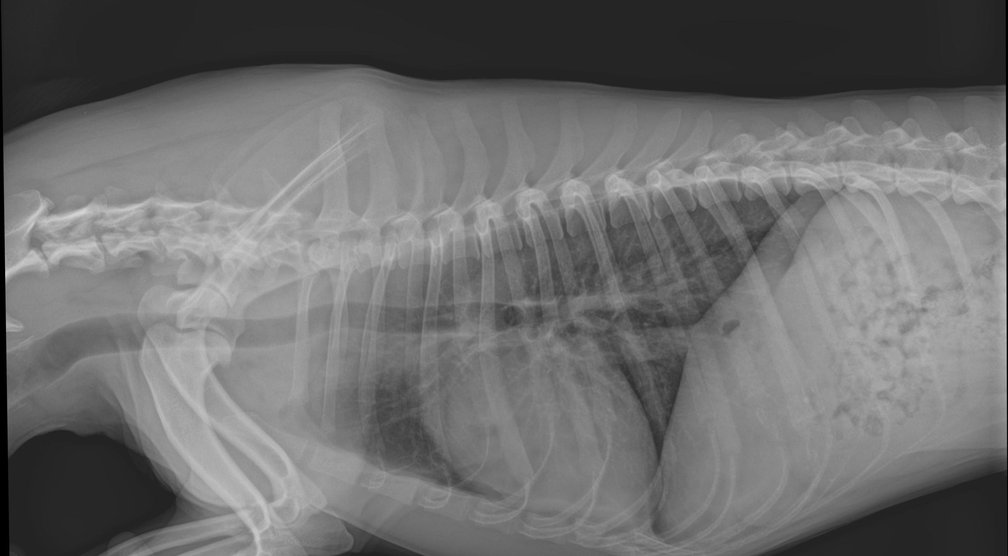

Afkomstig uit een dierenartspraktijk weten we hoe belangrijk dit is en dat beeldkwaliteit uw visitekaartje is.

Verbeteringen in verwerkingsalgoritmen, zelfs met behulp van kunstmatige intelligentie, helpen bij het stellen van een betere diagnose.